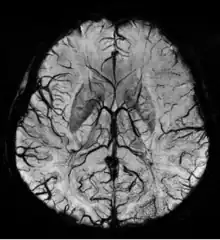

SWI venogram of a neonate with Sturge–Weber syndrome

An SWI venogram of a neonate with Sturge–Weber syndrome who did not display neurological symptoms is shown to the right. The initial conventional MR imaging methods did not demonstrate any abnormality. The abnormal venous vasculature in the left occipital lobe extending between the posterior horn of the ventricle and the cortical surface is clearly visible in the venogram. Due to the high resolution even collaterals can be resolved.